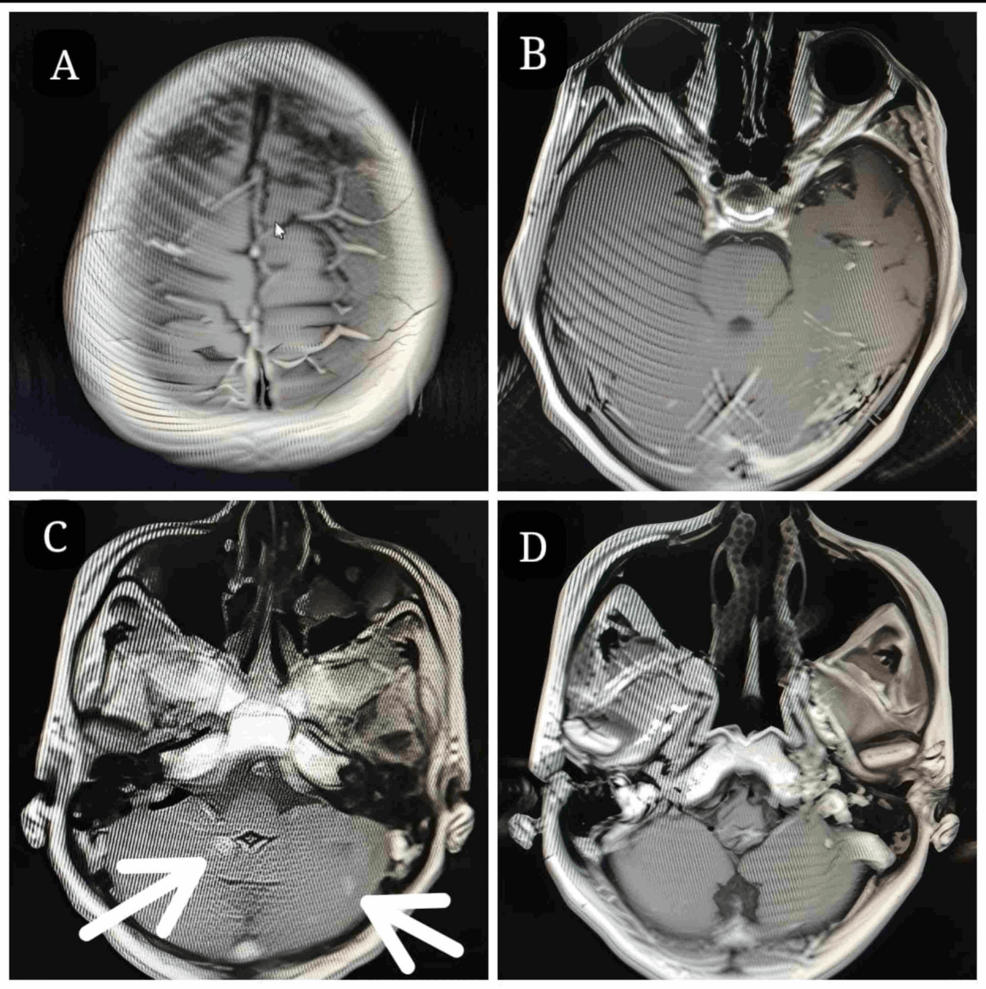

Just eight months later contrast MRI brain scans showed a remarkable overall lesion regression of 88%.

Most of the smaller intracranial lesions resolved completely, and there was a significant measurable reduction in target lesions.

Radiosurgery platforms are mainly classified as cobalt-based, LINAC-based, and robotic. There is no consensus to date upon which type of platform is suited to which kind of BMs. Gamma Knife makes use of cone-beam CT, while CyberKnife utilizes yet more effective six-dimensional skull-based motion trackers to monitor the patient’s position. In their contemporary review published in 2022, Skourou et al. concluded that Gamma Knife and CyberKnife provide an effective response at the cost of treatment duration [10]. Optimum delivery of maximum dose to GTV was achieved in our case, with minimal radiation to the peripheral tissue due to effective patient motion monitoring. This is evident from the clinical assessment, i.e., normal neurology and radiological follow-ups of our patient. Myrehuag et al. studied the effects of hypofractionated stereotactic radiation therapy upon 220 patients with 334 BMs and found local failure of 13% and 33% at 6 months and 12 months, respectively. However, with a 22 Gy dose, we achieved local control at the fourth and eighth months of follow-up with regression of lesions in our patient [11].